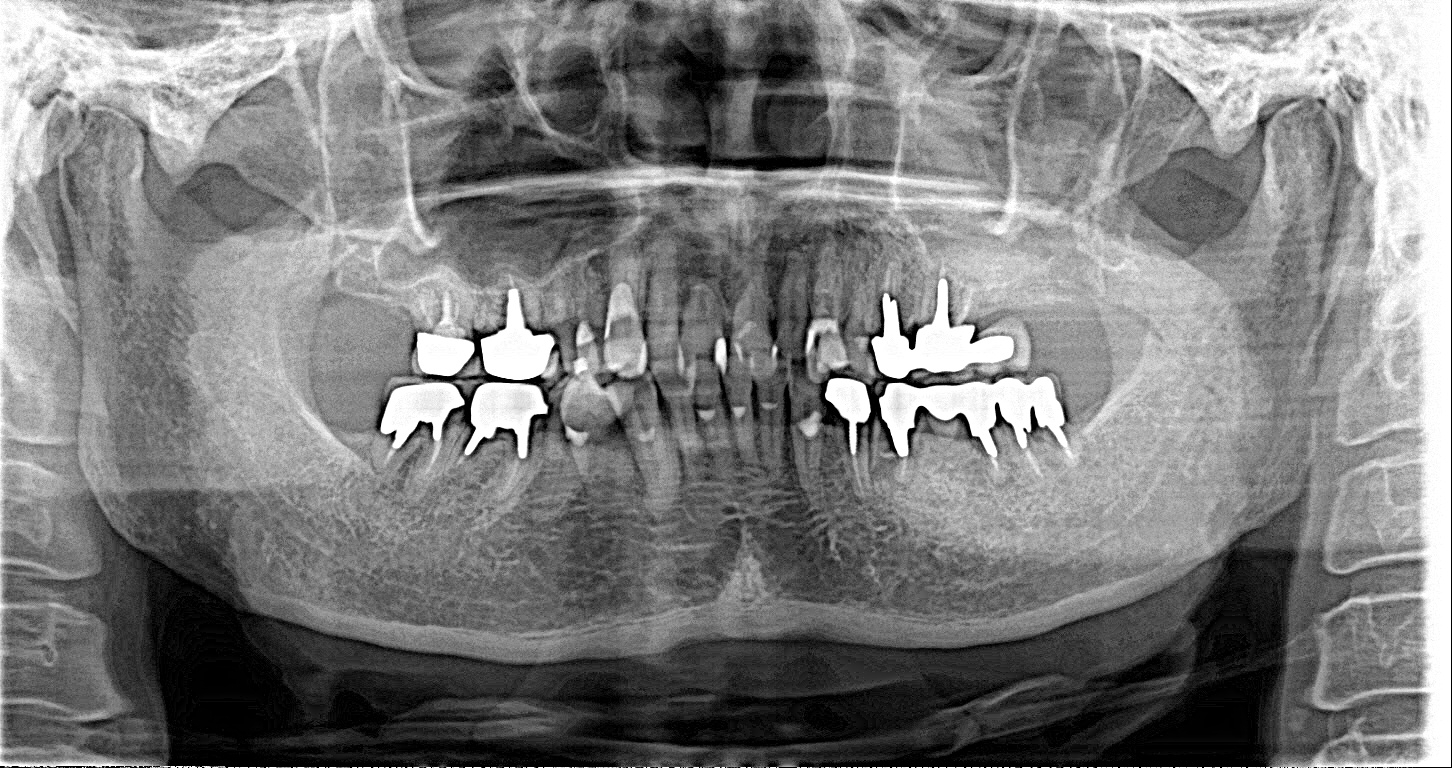

左下567番インプラントジルコニアアバットメント及びジルコニアセラミッククラウン装着